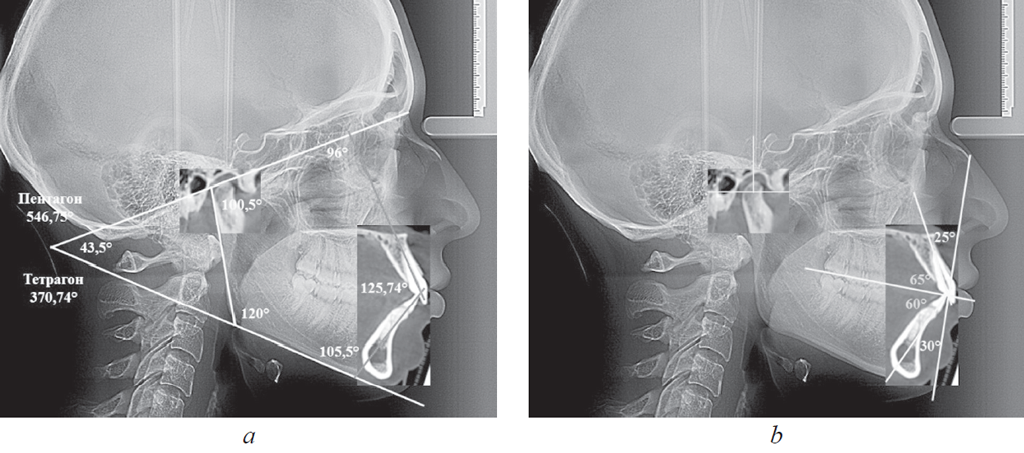

Рис. 3. Измерение гнатических углов (а); оценка положения сустава и резцов на совмещенных рентгенограммах (b)

Fig. 3. Measurement of gnatic angles (a); assessment of the position of the joint and incisors on combined radiographs (b)

Полученные снимки позволяли проводить линейные и угловые измерения, а также переносить данные томограмм на телерентгенограммы. Как отмечено выше, рекомендуем измерять угол между линиями МL и KFL, а также углы, образованные линиями резцов с указанными линиями (верхнерезцовый и нижнерезцовый). В совокупности с межрезцовым углом нами предложено оценивать сумму указанных четырех углов (тетрагональный показатель), их величины могут быть использованы для определения типа роста лицевого отдела головы. К такому же показателю можно отнести сумму пяти углов: верхнерезцового, межрезцового, нижнерезцового, нижнечелюстного и суставного (пентагональный показатель).

Наложение резцового зубочелюстного сегмента на боковую телерентгенограмму давало возможность определить торковые (вестибулярно-язычные) значения углов наклона резцов к окклюзионной плоскости (ОL). При этом по обе стороны от линии ОL в вертикальном направлении строили перпендикулярные линии, которые являлись ориентиром для измерения углов инклинации (торка) по отношению к окклюзионной плоскости.